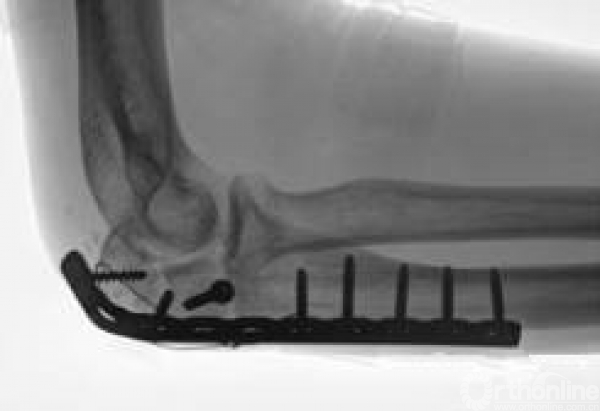

目前的主要治疗方法则分为钢板固定和张力带固定。

张力带骨折端压力真的只有1点点!但是钢板很强硬,一直有很好的表现,平均343牛的压力。钢板才是真的隐藏的牛牪犇啊!

动态测量中,这些骨折间压力。都是随着三头肌的收缩所减少的,所以作者认为还是要被动活动。至于为什么没有转化为压力,目前还没有人能彻底的搞明白……所以,大家以后还是用钢板吧,生物力学强!持续压力!当然还有别的原因。